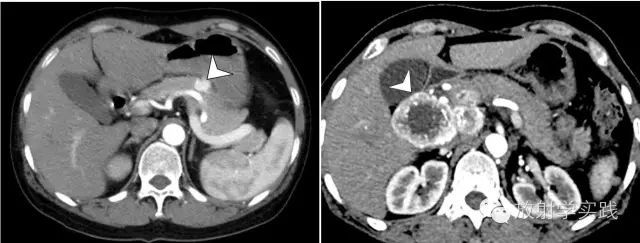

SPN本身为实性,但由于内部肿瘤的蜕变而形成大片囊性结构,而使肿块表现为实性、囊性或囊实混合外观,SPN被认为最易囊变的胰腺实性肿瘤[7]。SPN的实性区由大小均匀一致的小圆形细胞组成,T1WI为等低或低信号,T2WI为等高或高信号;实性成分向囊性成分过度区域则由大量假性乳头状结构交织排列而成的血窦构成,平扫T1WI等或等高信号,T2WI等或等低信号,增强后呈渐进性强化;囊性区域液化坏死组织T1WI低信号、T2WI高信号,出血的表现正好相反,是其特征性表现,发生率高[15](图5)。SPN囊实成分的分布也各不相同,可以表现为相间存在,也可以表现为实性成分位于周边,或者大小不等的多个囊腔位于肿块的边缘。

图5 胰腺实性假乳头状瘤(SPN)。a)T1WI增强动脉期,示胰头部肿块内可见出血(箭头)和实性成分(箭),实性成分呈轻度强化;b)延迟期示肿瘤实性成分明显强化(箭头)。